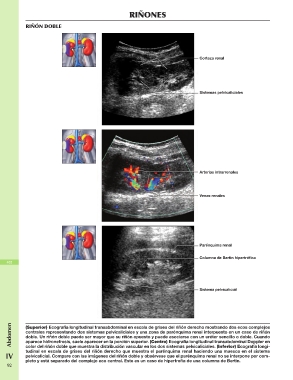

RIÑÓN DOBLE RIÑONES

Corteza renal

Sistemas pelvicaliciales

Abdomen Arterias intrarrenales

Venas renales

Parénquima renal

Columna de Bertin hipertrófica

Sistema pelvicalicial

(Superior) Ecografía longitudinal transabdominal en escala de grises del riñón derecho mostrando dos ecos complejos

centrales representando dos sistemas pelvicaliciales y una zona de parénquima renal interpuesto en un caso de riñón

doble. Un riñón doble puede ser mayor que su riñón opuesto y puede asociarse con un uréter sencillo o doble. Cuando

aparece hidronefrosis, suele aparecer en la porción superior. (Centro) Ecografía longitudinal transabdominal Doppler en

color del riñón doble que muestra la distribución vascular en los dos sistemas pelvicaliciales. (Inferior) Ecografía longi

IV tudinal en escala de grises del riñón derecho que muestra el parénquima renal haciendo una muesca en el sistema

pelvicalicial. Compare con las imágenes del riñón doble y obsérvese que el parénquima renal no se interpone por com

pleto y está separado del complejo eco central. Este es un caso de hipertrofia de una columna de Bertin.